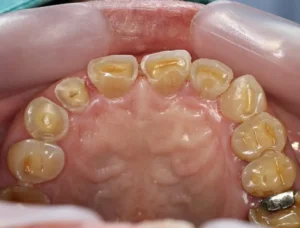

ذوبان الأسنان هو عملية تدمير تدريجي لمينا الأسنان، التي تعتبر أول طبقة تحمي الأسنان من التأثيرات الخارجية. يحدث ذلك نتيجة تفاعل بين الأحماض التي تنتجها البكتيريا في الفم والسكر. عندما تتناول الأطعمة والمشروبات الغنية بالسكر، تنمو البكتيريا وتنتج الأحماض، مما يؤدي إلى ذوبان المينا وفقدان المعادن. تظهر الحالة بشكل واضح على الأسنان كوجود بقع بيضاء، والتي هي علامة على بداية التآكل، وقد تتطور إلى ثقوب أو تجاويف إذا لم يتم التعامل معها بشكل مناسب.

يمكن أن تشمل أعراض ذوبان الأسنان زيادة حساسية الأسنان، خاصة عند تناول الأطعمة والمشروبات الساخنة أو الباردة. قد يشعر الأفراد أيضًا بألم في الأسنان، وفي بعض الحالات، يمكن أن يكون هناك تغير في لون الأسنان. يمثل ذوبان الأسنان تهديدًا لصحة الفم، لأنه يمكن أن يؤدي إلى مشكلات أخرى مثل العدوى أو تضرر اللثة. علاوة على ذلك، قد يؤثر تأثير ذوبان الأسنان على المظهر العام، مما يجعل الأشخاص يشعرون بالقلق حيال ابتسامتهم.